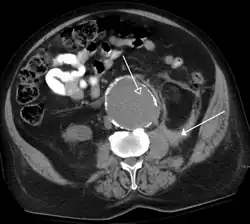

A CT scan image showing a ruptured abdominal aortic aneurysm.